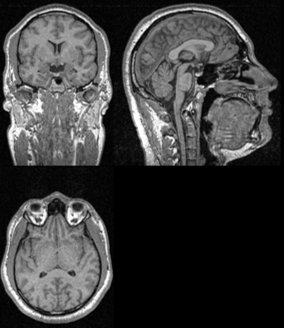

Figure 1: Left – Slice of an MRI scan with previews from Coronal (top left), Sagittal (top right), and Axial (bottom) planes. Right – The corresponding segmentation masks.

In order to derive reliable results from MRI data, a pipeline constituting multiple steps is required. One of these steps is Brain Extraction (also known as Skull Stripping), where the skull and other unwanted artifacts are removed from the scan; leaving behind only the brain. This allows the researchers to further process the brain scans without interference from the unwanted parts of the original scan.

We consider brain extraction as an instance of the Semantic Segmentation problem from the field of Computer Vision. That is, a function that implements brain extraction receives a scan as input and returns a binary mask where each pixel is either marked as brain or unwanted background.